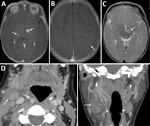

A 2-week-old infant was admitted to a hospital in Salt Lake City, Utah, USA, with lethargy, poor feeding, and pallor. The mother had ulcerative colitis in remission on infliximab therapy. One week after her infliximab dose at 34 weeks’ gestation, she experienced fever, sore throat, conjunctivitis, and cervical lymphadenopathy. After 6 days, a computed tomography scan of the neck revealed cervical lymphadenitis (Figure 1). An otolaryngologist evaluated and treated her with ceftriaxone and dexamethasone. She was evaluated by obstetrics 4 days later for decreased fetal movement. A biophysical profile score of 8 was reassuring. She underwent incision and drainage of her cervical lymph node. During the procedure, purulent fluid was encountered and sent for routine and acid-fast bacilli culture; no growth was noted at 4 days on routine culture or 42 days on acid-fast bacilli culture. She completed 10 days of amoxicillin/clavulanate.

Repeat lumbar puncture showed persistent lymphocytic CSF pleocytosis, and he underwent brain magnetic resonance imaging (MRI) with contrast. The MRI revealed 3 lesions, 2–7 mm in diameter, located in the left subthalamic nucleus, right thalamus, and left parietal cortex (Figure 1). Results of PCR testing of the CSF for toxoplasmosis were negative. Because of persistent illness and previously nondiagnostic evaluation, blood cfDNA testing (Karius) was performed, and results were positive for 804 molecules of microbial cfDNA/μL of F. tularensis DNA most aligned with subspecies holartica (Table 2). Treatment with intravenous (IV) ciprofloxacin and gentamicin was initiated.

The infant received 1 week of IV gentamicin and 4 weeks of IV ciprofloxacin. Near the end of therapy, repeat microbial cfDNA testing (Karius) demonstrated a marked decline in F. tularensis microbial cfDNA levels (Table 2). Repeat brain MRI with contrast showed near complete resolution of the previous lesions with only “trace residual focus of enhancement in the left subthalamic region.” He remains well, last evaluated at 15 months of age.